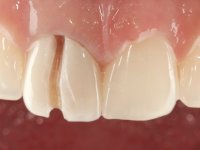

Female patient, 33 years old, non-smoker. Tooth 11 with endodontic treatment rehabilitated with a crown. This crown shows an infiltrated cervical interface. The smile line was high, this area being very visible. The patient had a thick gingival phenotype and good oral hygiene.

The patient was asked to remove the infiltrated crown and make a new crown with a ceramic-coated Zr infrastructure. As aesthetically, the crown was very well achieved, the patient and her dentist showed doubts about the need or not to intervene immediately. After clarifying my position on the infiltrated interfaces, we decided to jointly intervene. In these situations, the sooner you intervene the better